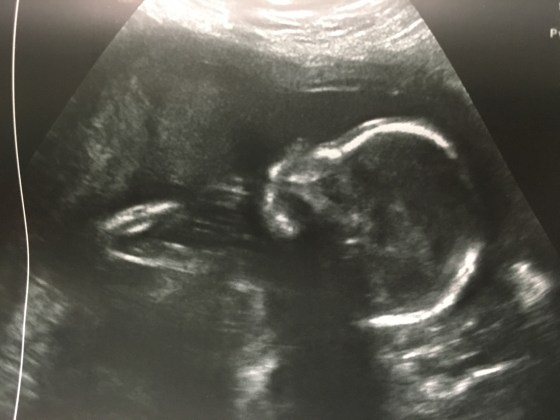

Baby Update 20 weeks

Praise Jesus! Today we had our 20 week appointment and the echogenic bowel is gone. All the blood tests came back normal and the ultrasound today showed a perfect baby!

I’m starting to feel regular kicks but not a lot. Mostly at night or when I’m wearing a seat belt. The doctor says the baby is breach and is sitting on its feet. They still haven’t been able to count toes because they are always hidden under the booty.